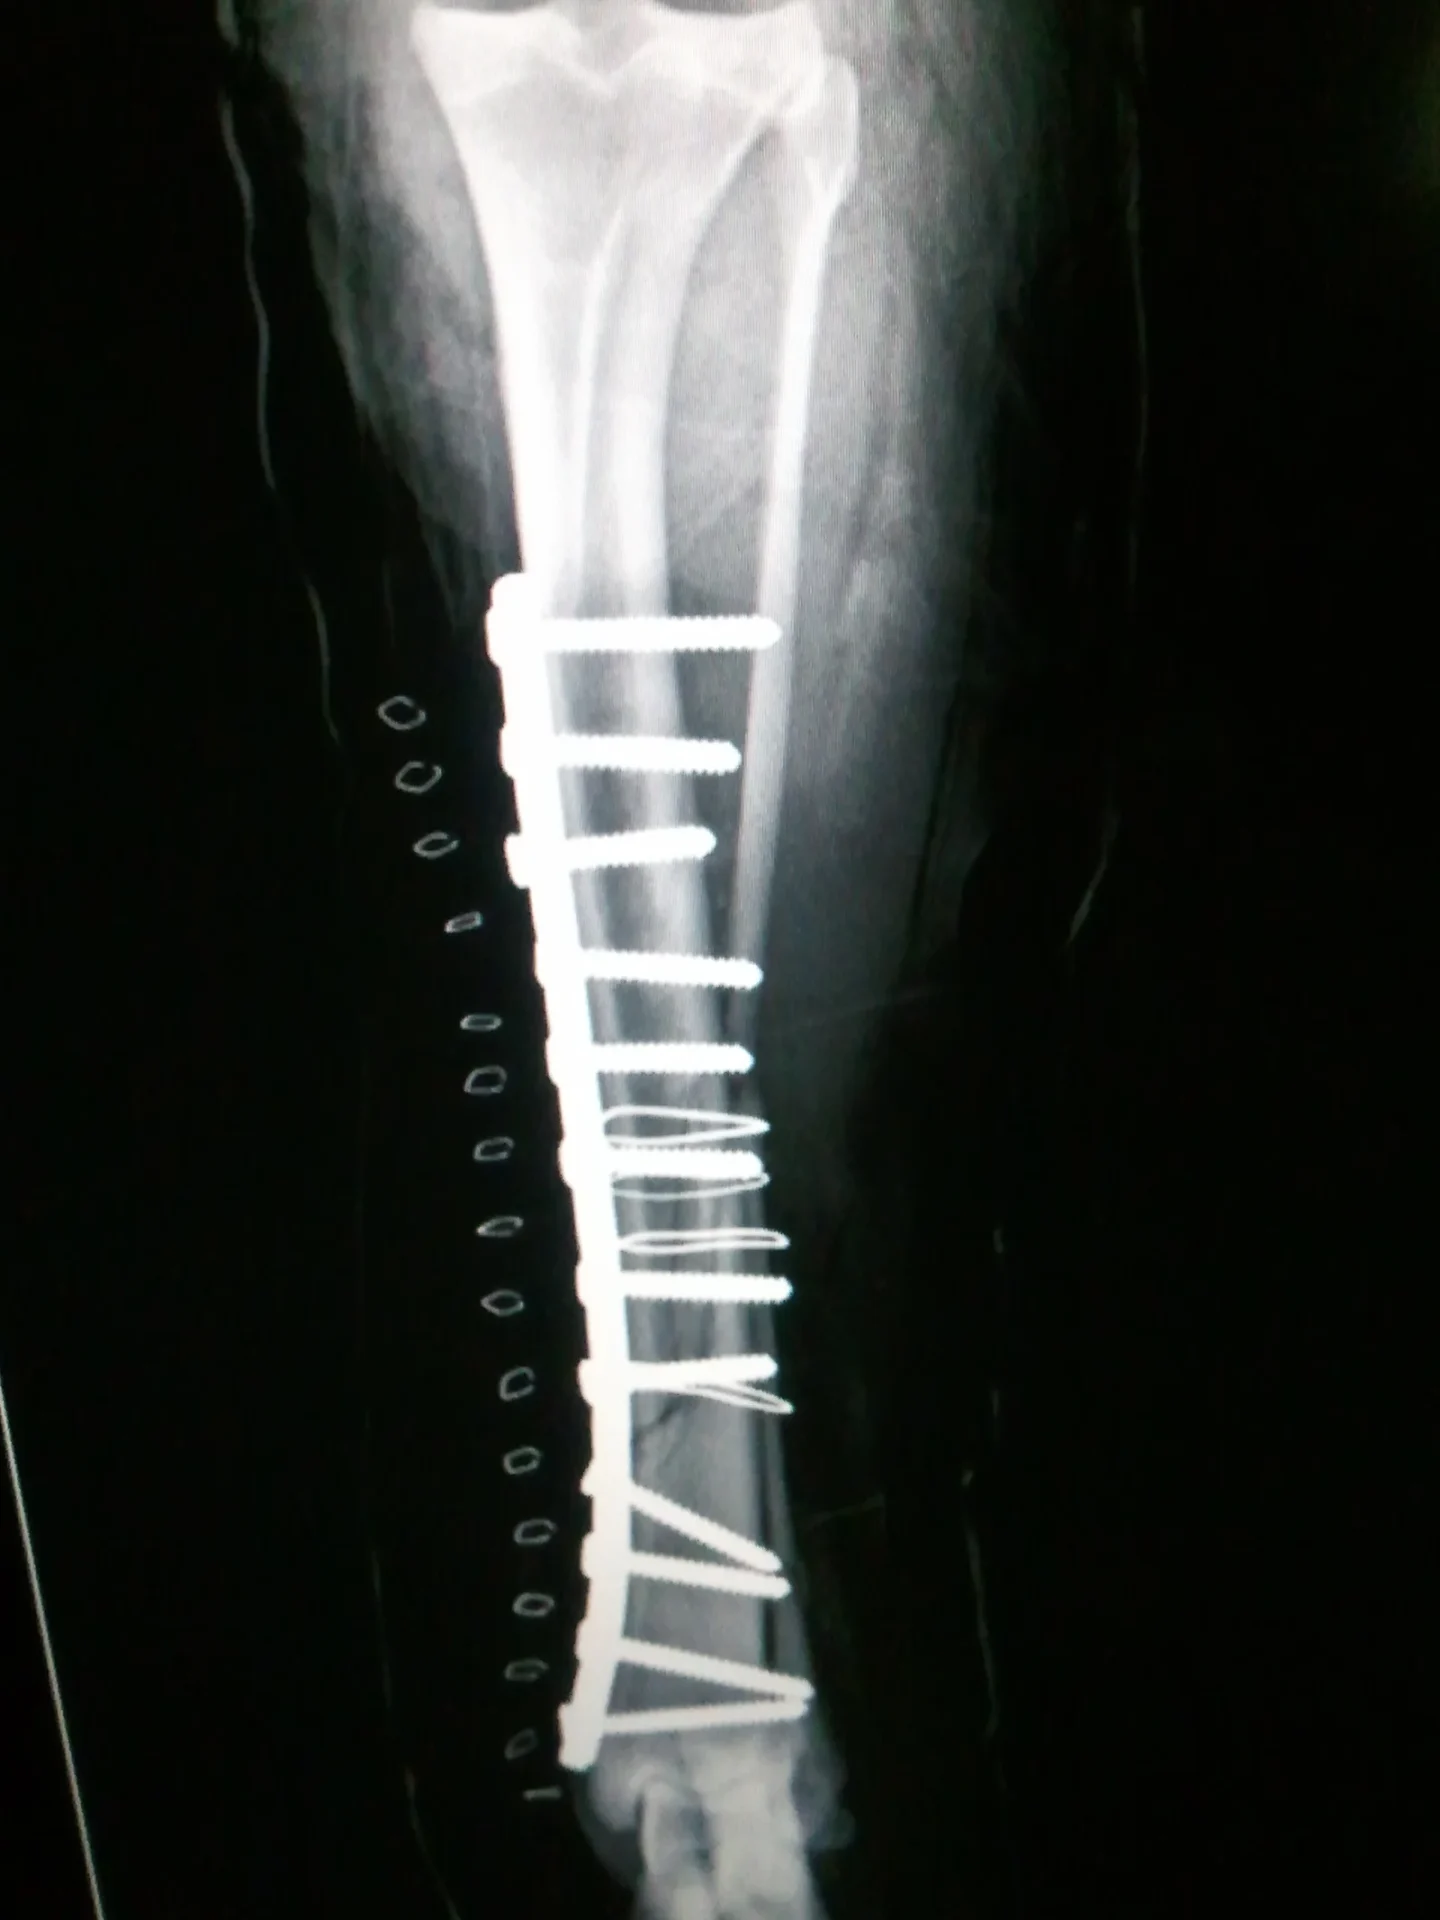

Galería de casos clínicos

Casos clínicos de cirugía (tejidos blandos, traumatología, neurocirugía, artroscopia)